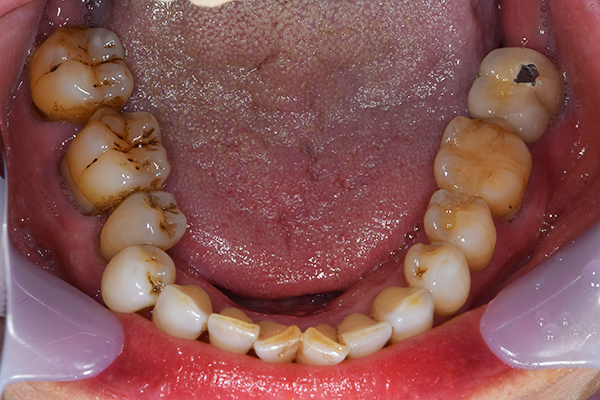

ケース2(自費の総入れ歯と部分入れ歯)

上下の入れ歯が外れやすくなったということでいらっしゃいました。 顎の骨はしっかりしていましたので、精密な型取りさえすればしっかりした入れ歯がつくれると思いました。 また下には6本歯が残っていましたが、虫歯になっている歯もありました。 かぶせ物のなかで大きな虫歯があった歯があり、1本だけ残せない状態でした。

上の入れ歯は確かに吸着は甘くなっていました。 また下の入れ歯はバネの一部が壊れており、安定感がなくなっていました。

精密な型取りの後、噛み合わせのチェックをしていきました。 かぶせ物も同時に作っていきました。

歯を並べた後、かぶせ物のフレーム作ってもらいました。先に歯を並べて理想の位置を決めておくことが大切です。

完成した入れ歯とかぶせ物です。 入れ歯への寛容度が高い患者様でしたので、 金属は使用せず、プラスチックのみで上は仕上げました。 下顎も歯は1本減ってしまいましたが、しっかり 入れ歯が維持できる様な構造にしました。

お口の中に入れた状態です。 見た目も最初とほとんど変わることなく作成できました。 維持や吸着に関しても問題ないようでした。

年齢 80歳・女性

主訴 上下の入れ歯が外れやすくなった

治療期間 3ヶ月

治療費 .メタルボンドクラウン:550,000円

.義歯:990,000円(税込、上下)

治療方針 長年使ってきた義歯の人工歯が磨耗し、臼歯部での咬合がすくなくなり、入れ歯の安定も悪くなり、あたりどころが悪くなって痛みが出ている。 そのため、入れ歯を上下作りかえる必要がある。

治療内容 過去に治療を行ったことのある歯が再度虫歯になってしまっているところがあり、すでに残せない状態にまでなっていたため、歯を一本抜歯した。 その後、かぶせ物と入れ歯を同時に作成していった。

特記事項 歯を抜いた後は、2〜3ヶ月歯ぐきの回復を待ってから入れ歯を作るため、待機期間があります。その間、古い入れ歯を調整しながらそのまま使うか、新し物をつくっておく必要があります。ただし、入れ歯は保険治療で作成する場合、6ヶ月は新しいものが作れないという決まりがあるので保険で全て作りたい場合は注意が必要です。